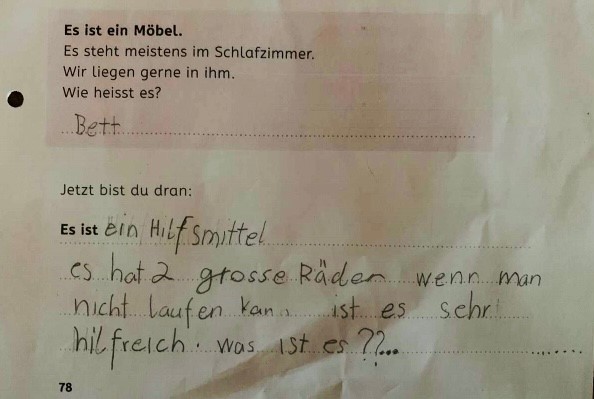

"TYPISCH ANGELMAN" ist ...!

Aktion zum internationalen Angelman Tag 2025

Unsere Aktion heisst auch dieses Jahr: "Typisch Angelman" ist ...